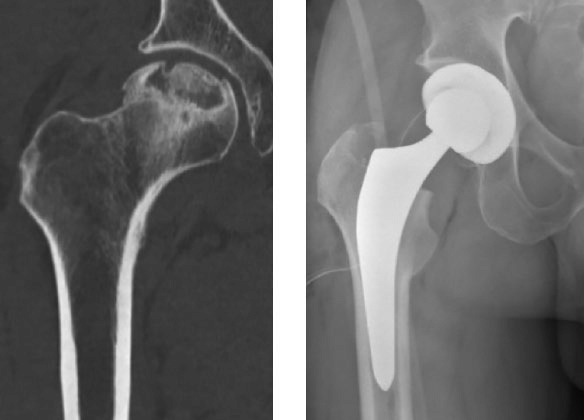

Artroplastie protetică

- Majoritatea pacienților cu colaps femural necesită în cele din urmă o intervenție reconstructivă, cel mai frecvent o formă de artroplastie.

- Artroplastia totală de șold este cea mai eficientă metodă de ameliorare a durerii în NAV avansată.

- La pacienții tineri, se preferă metode care preservă osul și întârzie protezarea totală.

🔹 Artroplastia totală de șold:

- Cel mai utilizat și cu cele mai bune rezultate în NAV avansată.

- Rezultate mai modeste decât în coxartroză.

- Protezele necimentate moderne par să aibă durabilitate crescută.

- Contraindică activitățile cu impact (ex: alergat), care pot scurta durata de viață a implantului.